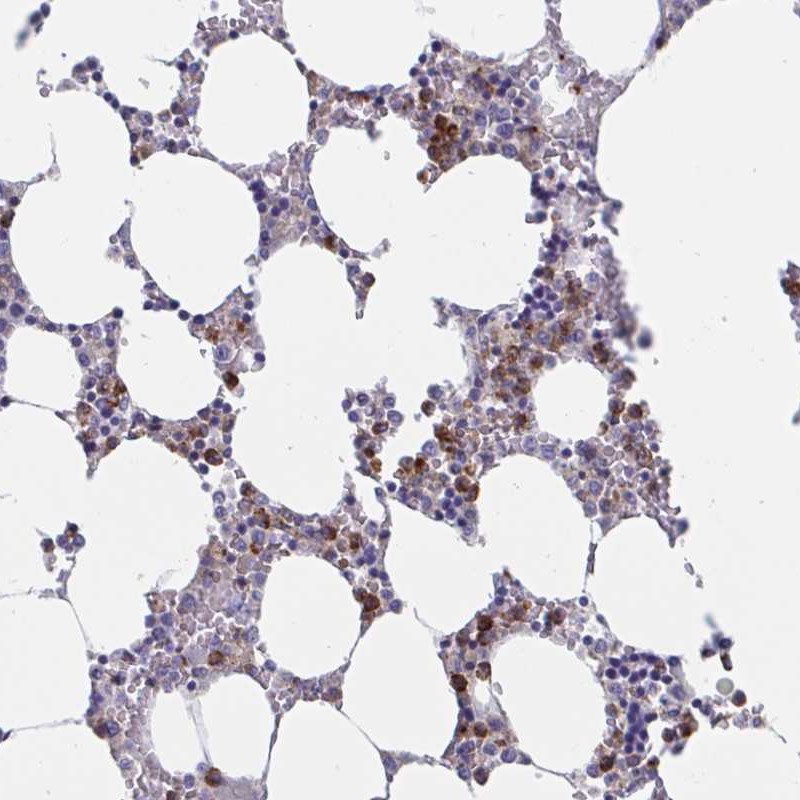

Immunohistochemical staining of human bone marrow shows strong cytoplasmic positivity in hematopoietic cells.